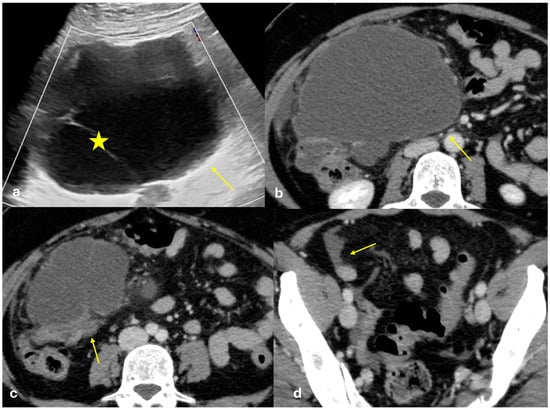

3.3.6. Peritoneal Tuberculosis